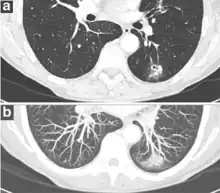

Thin slice and maximal intensity projection of a lung nodule, the latter better visualizing vascular convergence.[9]

• Vascular convergence is where vessels converge to a nodule without adjoining or contacting the edge of the nodule, and is mainly seen in peripheral subsolid lung cancers.[9] It reflects angiogenesis.[9]

Air bronchograms is defined as a pattern of air-filled bronchi on a background of airless lung, and may be seen in both benign and malignant nodules, but certain patterns thereof may help in risk stratification.[9]